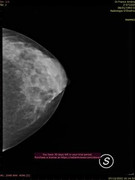

Parenchimi fibroghiandari con componente adiposo nei quali l'esame ecografico integrato da esame mammografico non ha evidenziato aspetti patologici,anche nell'area di maggiore densità parenchimale nel q superiore est di sn. Si consiglia un controllo ecografico fra 6 mesi salvo diversa indicazione clinica.

Queste sono le.immagini della mammografia,e ricordo sempre il motivo oer la quale ho fatto tutti questi accertamenti,presenza di un nodulo o pallina seno sinistro,chr a quanto pare rivelatasi mia conformazione del seno. (Come già da lei ribadito)